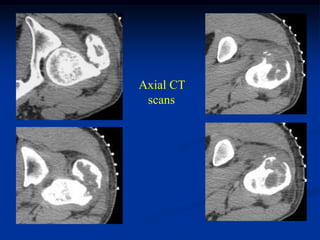

Case #124

11 year male

chondromyxoid fibroma

proximal tibia

Case # 124.1                    AP and lat x-ray

50 year male with chondromyxoid fibroma proximal

tibia with 6 months of a tender tumor mass anterior tibia

Coronal T-1 MRI

Coronal PD FS MRI

Axial PD FS MRI

Axial Gad MRI